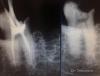

Каплан Опубликовано 19 марта, 2013 Поделиться Опубликовано 19 марта, 2013 (изменено) 26. асимтоматичен. ранее попытка ретрита, пройден мезиальный. (по снимку 1). и немного небный. зная что резорцинка, думаю сниму пломбу, гляну что и как, если что просто переставлю и все.открыл. локализовал устья. нашел пропущенный мезиальный. распаковал гутту в мезиальном и небном. бился бился в небный, не идет. дистальный до упора. мезиальный (запакованный) до апекса, найденный до упора. кальций.пришла в след.визит. я опять с мыслью отмою и запакую.в итоге прошел небный (канал был чуть дистальнее, мезиальнее ступенище). дистальный до упора. под занавес запикал потеряшка-мезиальный... и вот в самый последний момент, смотрю, а в мезиальном еще кусок гутты, который мне не нравится. я его спредером ковырнул, а там прям канал. обработка до упора.итого 3 мезиальный, дистальный и небный. кальций.сегодня запаковал.http://img855.imageshack.us/img855/2899/68794825.jpg Uploaded with ImageShack.ushttp://img842.imageshack.us/img842/4233/88379552.jpg Uploaded with ImageShack.us Изменено 19 марта, 2013 пользователем Каплан 12 Ссылка на комментарий

Мартовский Опубликовано 19 марта, 2013 Поделиться Опубликовано 19 марта, 2013 Супер, особенно апикальный контроль в небном Ссылка на комментарий

Каплан Опубликовано 19 марта, 2013 Автор Поделиться Опубликовано 19 марта, 2013 Супер, особенно апикальный контроль в небномспасибо. в небном правда не так плотно как хотелось бы но это максимум что я смог выжать. Ссылка на комментарий

Каплан Опубликовано 19 марта, 2013 Автор Поделиться Опубликовано 19 марта, 2013 (изменено) Отличная работа!Всегда с удовольствием смотрю ваши кейсы!Каким образом обошли ступенище в небном?Спасибо если честно- я сам не понял как это вышло. дело в том, что во второй визит я работал в бино, подсветил, увидел две точки и два хода. один ложный где ступень, вторая точка дистальнее, в которую я бился и не мог пройти. потом просто ткнул файлом и прошел на снимке с метапастой видно где ход канала а где ступень и ложный ход. Изменено 19 марта, 2013 пользователем Каплан Ссылка на комментарий

DmitrySH Опубликовано 19 марта, 2013 Поделиться Опубликовано 19 марта, 2013 На снимках кажется что там дыра Ссылка на комментарий

Денис481 Опубликовано 20 марта, 2013 Поделиться Опубликовано 20 марта, 2013 не плохо,но апекс все же не нравится на небном,ну думаю это максимум что можно выжать из него,и снимок где 3 канала почему в такой проекции? он на небный накладывается и нечего не видно....на остальных снимках хорошо видно а на последнем нет... Ссылка на комментарий

Каплан Опубликовано 20 марта, 2013 Автор Поделиться Опубликовано 20 марта, 2013 (изменено) не плохо,но апекс все же не нравится на небном,ну думаю это максимум что можно выжать из него,и снимок где 3 канала почему в такой проекции? он на небный накладывается и нечего не видно....на остальных снимках хорошо видно а на последнем нет...что не так с апексом на небном? Он открывается вбок, петтенси получил, стопупор четкий, 40.02. обработка на всю длину до 35.04. кусок апекса откушен природой-матушкой... гутташтифт встал мертво, остальные допаковал под линеечку...последний снимок развернут специально, что бы разделить каналы в мезиальном, остальные меня не интресовали уже на тот момент. дистальный не интересовал даже теоретически, потому как там упор и ап.лок молчит.на снимке отмечен цифрой 1 пропущенный, 2 и 3 - те что были с гуттой. 3й самый буккальный... и да, я не фотошоплю снимки. вообще. даже контраст не трогаю. исключение, если нужно что-то конкретное ткнуть на снимке (как на последнем), но контраст все равно не трогаю. все снимки выставлены в том виде, в каком они есть на самом деле... Изменено 20 марта, 2013 пользователем Каплан 1 Ссылка на комментарий